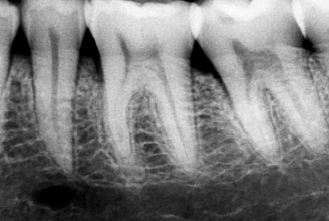

1- Grado de calcificación de la cámara pulpar y conductos

radiculares

La fisiología pulpar puede desarrollar diferentes grados de

calcificación de la cámara y de los conductos radiculares.

Esta calcificación se debe generalmente a un estímulo

o noxa como puede ser una caries o el desgaste de la pieza dentaria

por atrición a través del tiempo. Existen otros tipo de

calcificaciones a nivel del conducto, que no son explicadas por

estímulo alguno.

Se sabe que a edades de entre 70 y 80 años los conductos se

hallan muy calcificados, lo cual implica un desafío para hallar e

instrumentar dichos conductos.

La radiografía periapical es imprescindible para visualizar el

grado de calcificación de la cámara o conducto radicular. Usted

puede modificar el tiempo de exposición de la película radiográfica

(disminuyendo o aumentando la dosis de RX) y verá que aumenta o

disminuye el grado de calcificación de dicha imagen de la pieza dental.